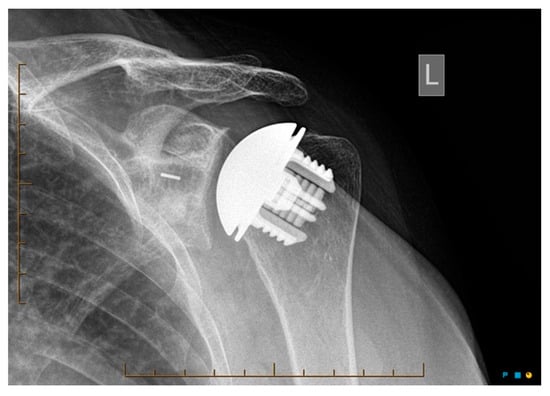

Radiological outcomes are outlined in Table 3. Twenty-six participants had radiographs available for review at a mean follow-up of 64 weeks. No component significantly loosened, migrated, or subsided. All glenoid components were grade 0. Ultimately, 21 of the 26 participants and 17 of 26 participants had anteroposterior and axillary views respectively available for review. For the humeral component, radiolucencies were minimal and located in zones 1, 5, 6, and 10. Figure 5 displays an anterior to posterior post-operative X-ray, and Figure 6 displays an axillary lateral post-operative X-ray showing the anchorpeg position.

Figure 6.

Axillary-lateral post-op X-ray showing anchorpeg position, 24-month post-operative. Female participant aged 60 years.